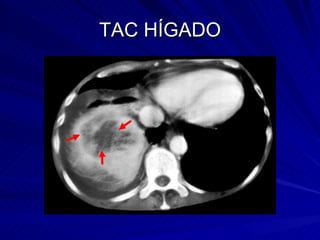

TAC HÍGADO

TAC HÍGADO Aire en el sistema porta